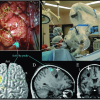

Neurology

Neurological disorders are the kind of diseases that disturb the brain or autonomic a...